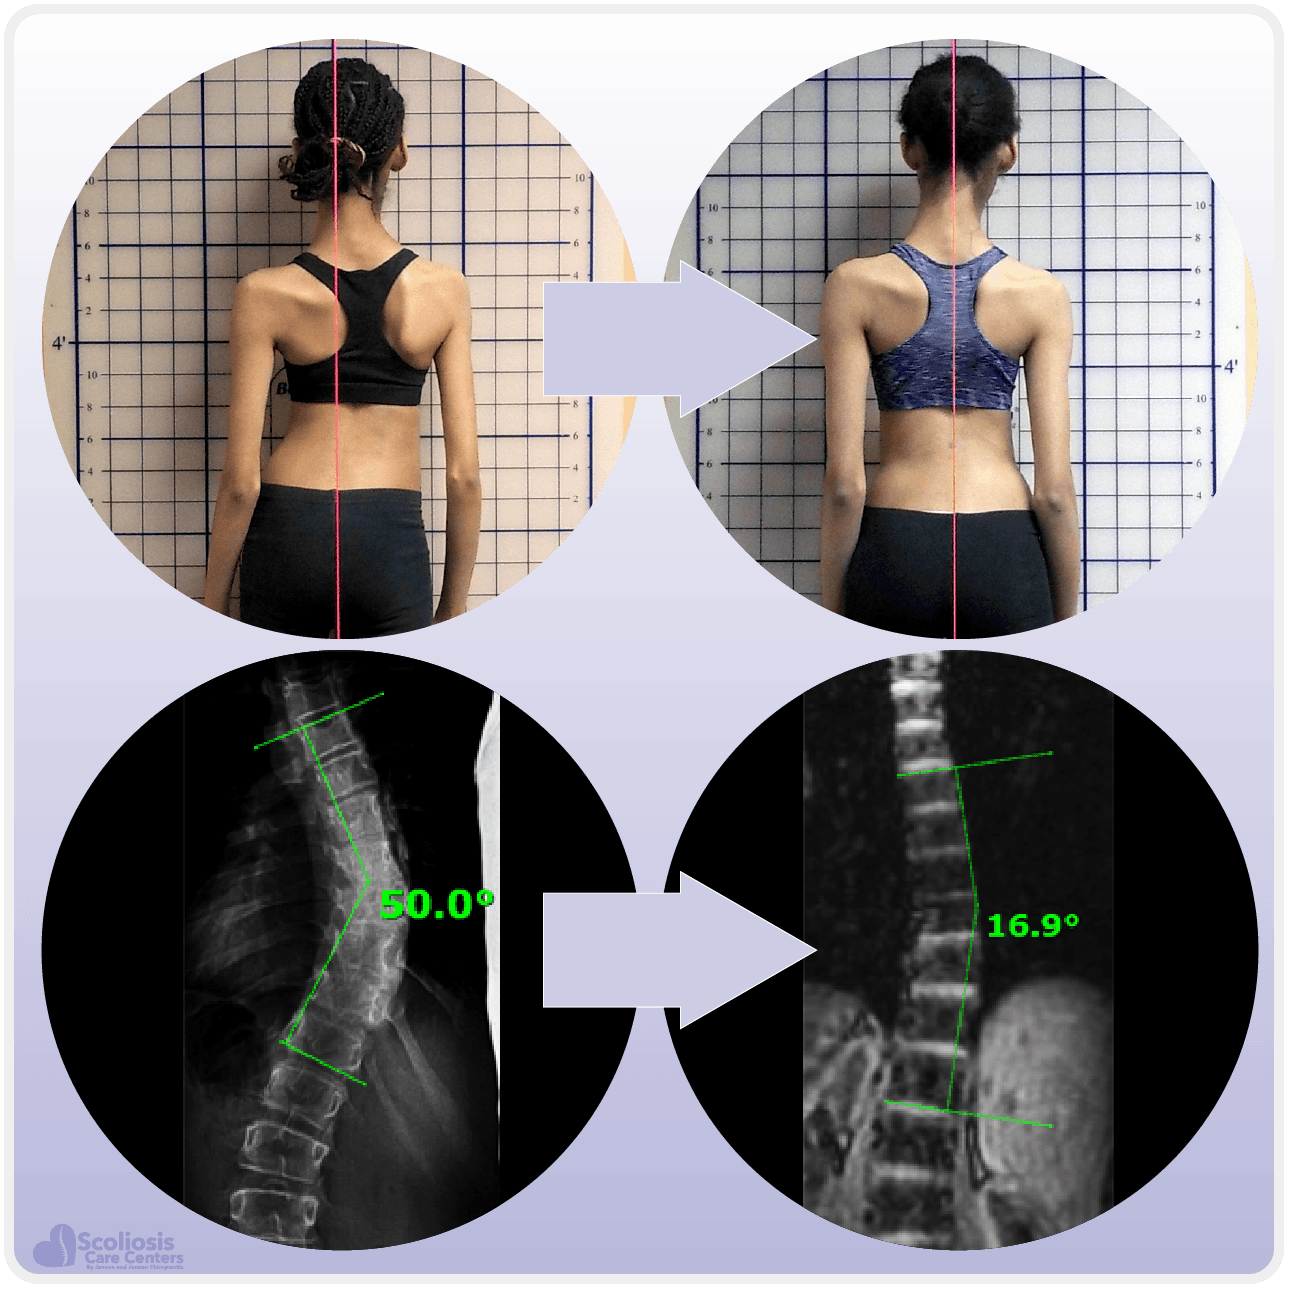

إذا كان الحبل الشوكي الضيق يحدد مدى التصحيح الجراحي، فهل يمكن أن يؤثر أيضًا على العلاجات غير الجراحية مثل التمارين والعلاج بالحزام؟ الإجابة نعم. كثير من مراكز علاج الاعوجاج تطور حاليًا برامج تهدف إلى زيادة مرونة الحبل الشوكي وتمديده تدريجيًا، ما يمنح التمارين والحزام فرصة أفضل لتحقيق نتائج ملحوظة.

تحسين مرونة الحبل الشوكي يشبه “إخماد النار” التي تسببها قوة الشد: كلما زادت مرونة الحبل، أصبح من الأسهل على الحزام والتمارين المساعدة في إعادة توازن العمود الفقري بدون المخاطرة بالشلل.

العلاج غير الجراحي: استخدام أحزمة طبية مخصصة وتمارين لتقوية العمود الفقري وزيادة مرونة الحبل الشوكي.

المتابعة المستمرة: تصوير دوري بالأشعة لمراقبة الانحناء ومدى التقدم في العلاج.